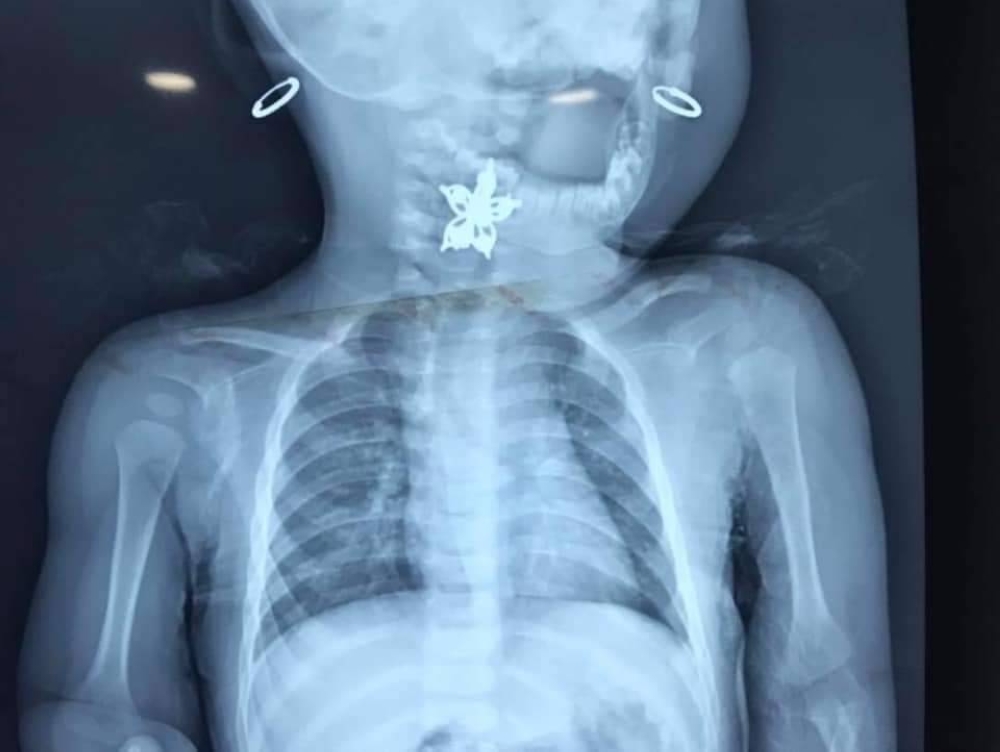

وبمتابعة دقيقة من طبيبي الجراحة والأطفال الدكتور علاء الزيود، والدكتور سيف الخوالدة، تم فحص الطفلة بعناية فائقة، إذ تم اكتشاف جسم غريب قريب من حلق الطفلة، ما أدى إلى تعامل الفريق الطبي مع الموقف بسرعة واحترافية، ليتم استخراج الجسم الغريب والذي تبين أنه مشبك شعر بلاستيكي.

وأضاف أن الأطباء أجروا صورًا شعاعية للتأكد من عدم وجود أجسام أخرى قد ابتلعتها الطفلة، بالإضافة إلى فحوصات طبية شاملة، وبعد التأكد من استقرار حالتها تم إخراجها من المستشفى وإعطاؤها مضادات حيوية وقائية لتفادي أي التهابات محتملة نتيجة الخدوش الناجمة عن الجسم الغريب.